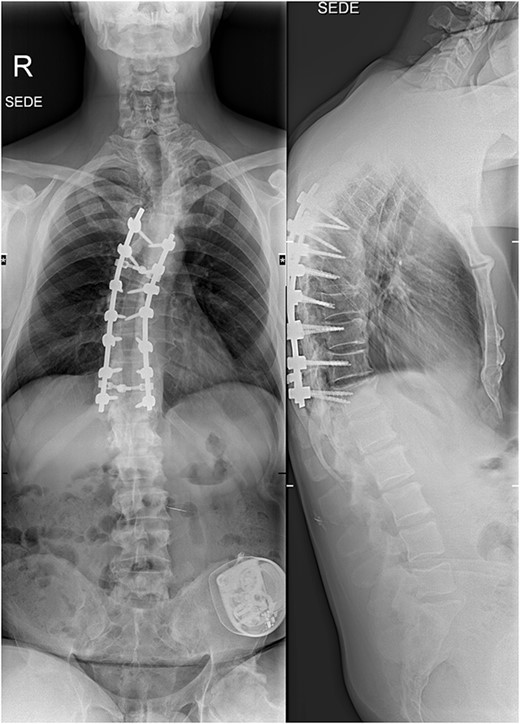

The imaging studies revealed thoracic kyphoscoliosis (with a kyphotic curve of 50°, left upper-thoracic curve of 40° and right lower-thoracic curve of 25°) and significant stenosis of the thoracic part of the spinal canal (particularly at levels Th6, Th9 and Th11) due to severely ankylosed ligamentum flavum (OLF) and the concomitant degeneration of the facets (Figs 1 and 2). Imaging indicated thoracic myelopathy (Fig. 3). We performed emergent posterior wide laminectomy using an ultrasound bone scalpel, and a partial correction of the deformity by instrumented spinal fusion (Th6-Th12). The surgery was performed by the senior author (N.H.).

The initial CT scan (axial views), showing the width of the spinal canal at Th6 (above), Th9 (middle) and Th11 (below).